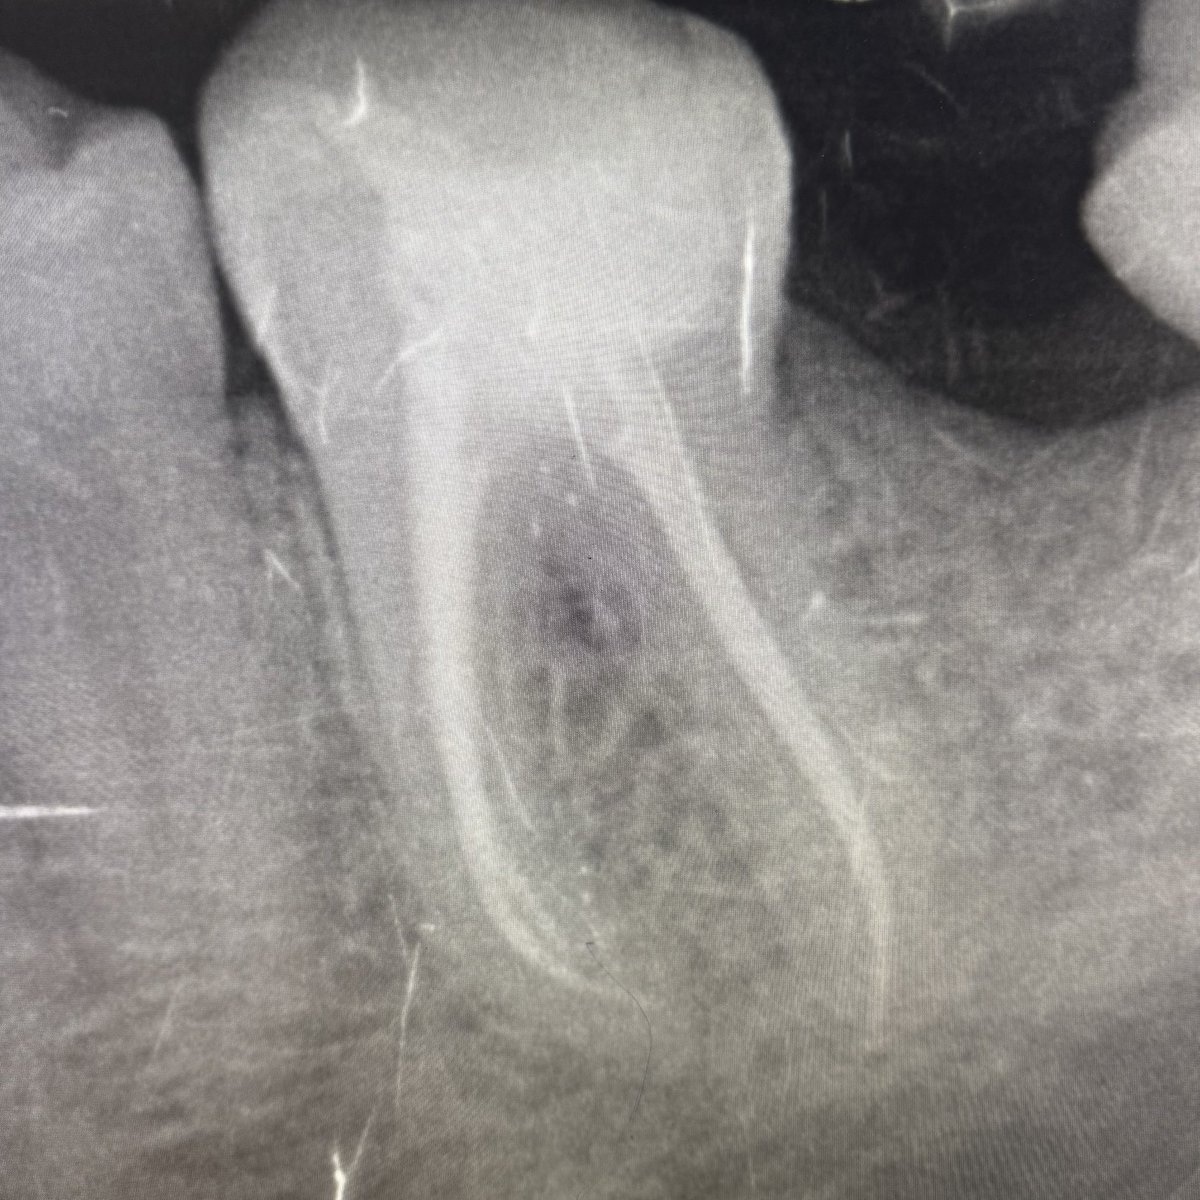

Finalllyy Sep&October’s case 🤩

Cc :“i have severe pain on my upper anterior tooth while drinking cold“

MH : ASA II

DH : multiple Extractions

after IOE : #12 was diagnosed“Asymptomatic irreversible pulpitis with symptomatic apical periodontitis“

Tx : RCT,post&core and crown